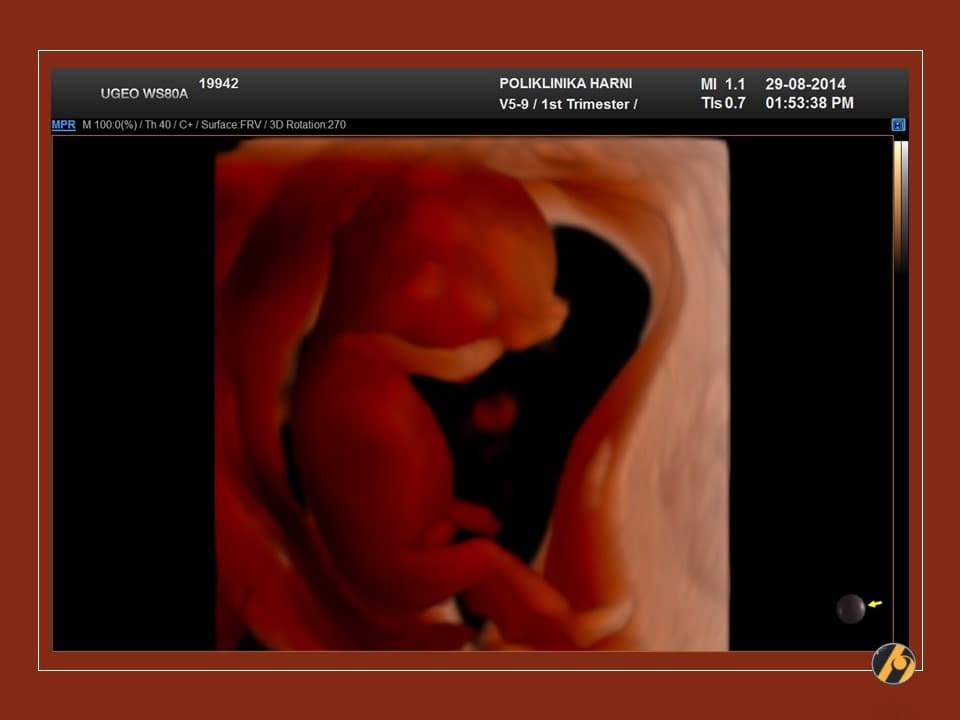

Glava vaše bebe još uvijek svojom veličinom nadmašuje tijelo, i čini gotovo cijelu polovicu dužine tijela. Razlog tomu je veoma rani početak razvitka mozga. Sada se uši postupno premještaju od vrata prema njihovom mjestu na glavi.

Napreduje razvitak ostalih organa. U trbuhu se intenzivno razvijaju crijeva, koja se nerijetko mogu vidjeti ultrazvučno i u pupčanoj vrpci / fiziološka omfalokela što je za ovaj period embriogeneze sasvim u redu. Crijeva se tijekom narednog tjedna vraćaju sasvim na svoje mjesto, u trbuh.

Razvija se mišićni sloj stijenke crijeva, koja stoga pokazuju peristaltiku - valove kontrakcija koji potiskuju hranu kroz crijevo. Dovršava se razvitak vanjskog spolovila vaše bebe.

Vaša beba dugačka je 4.5 - 6.0 cm, a teška je 8 - 10 g.